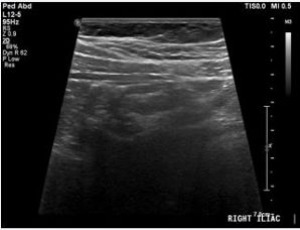

Abstract Objectives: An early and precise diagnosis is important to confirm acute appendicitis (AA) in children. Ultrasound imaging techniques have demonstrated higher value in the diagnosis of AA. This study was conducted to ascertain the nondiagnostic and..... -